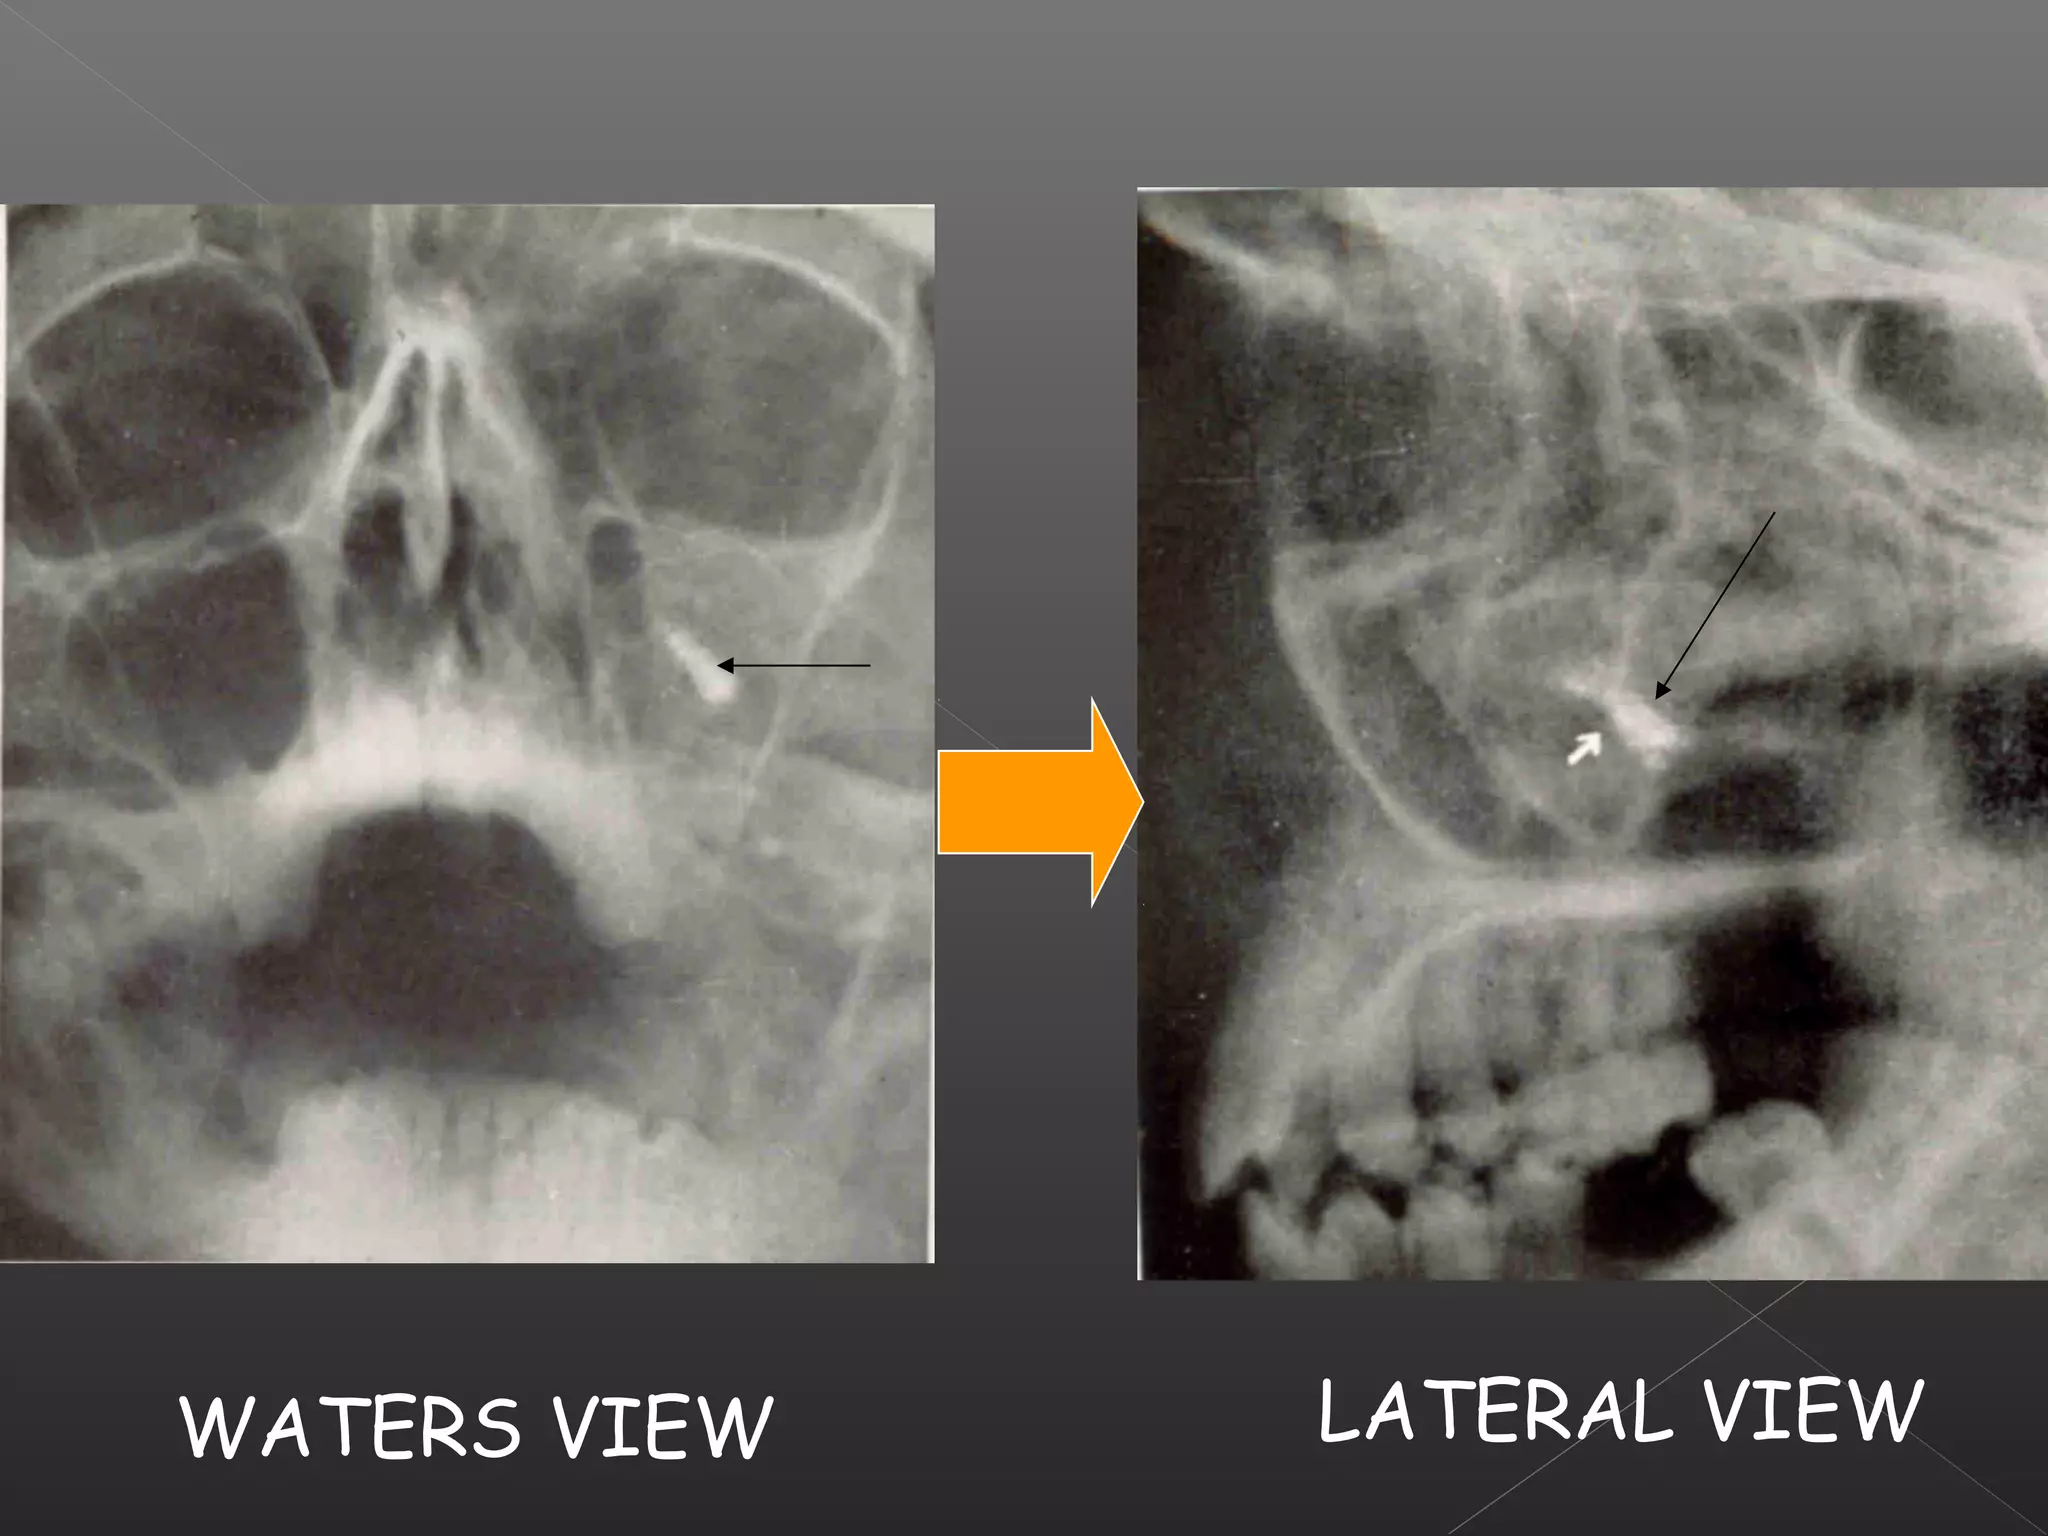

This document discusses techniques for localizing objects using radiography. It describes common reasons for needing to localize foreign bodies or other objects like unerupted teeth, fractures, or tumors. Two main techniques are described: Miller's technique which uses two radiographs at right angles, and Clark's tube-shift technique which analyzes how an object's image shifts when the projection angle is changed. The advantages and disadvantages of each technique are provided.